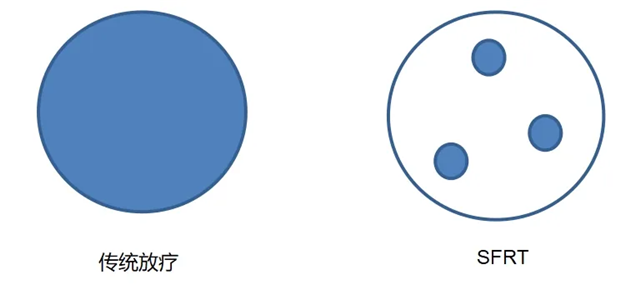

空间分割放疗(SFRT)是一种前沿的放疗技术,它巧妙地在肿瘤中心聚焦极小范围的高剂量(峰剂量),而在肿瘤周边则施以相对低剂量(谷剂量),这种交替分布的设计,不仅直接杀灭肿瘤细胞,还能激活机体抗肿瘤免疫反应,从而达到既能控制肿瘤,又能最大程度保护正常组织,还能增强免疫治疗疗效的目的。空间分割放疗效果显著,尤其对那些常规放疗不敏感的巨大肿瘤具有独特优势。

填补大体积肿瘤治疗空白,提高肿瘤局部控制率,并激活机体的抗肿瘤免疫反应。

相比传统放疗,空间分割放疗(SFRT)能显著减少放疗后的不良反应,提升患者的耐受性。